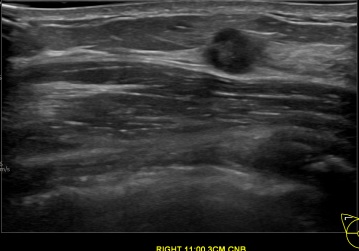

상기환자는 만져지는멍울있어 내원하신 50대 후반

여성분으로 의심스러운 우측유방혹 조직검사 시행해 유방암 진단되었습니다.